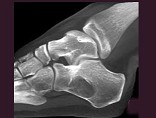

- 单项选择题男,32岁, 几天前踝部扭伤,疼痛, 不能行走,结合CT图像, 最可能的诊断是 ( )

A、骨囊肿

B、动脉瘤样骨囊肿

C、骨纤维异常增殖症

D、骨巨细胞瘤

E、畸形性骨炎